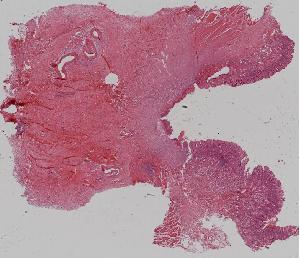

33. Papillar transitional carcinoma of the bladder